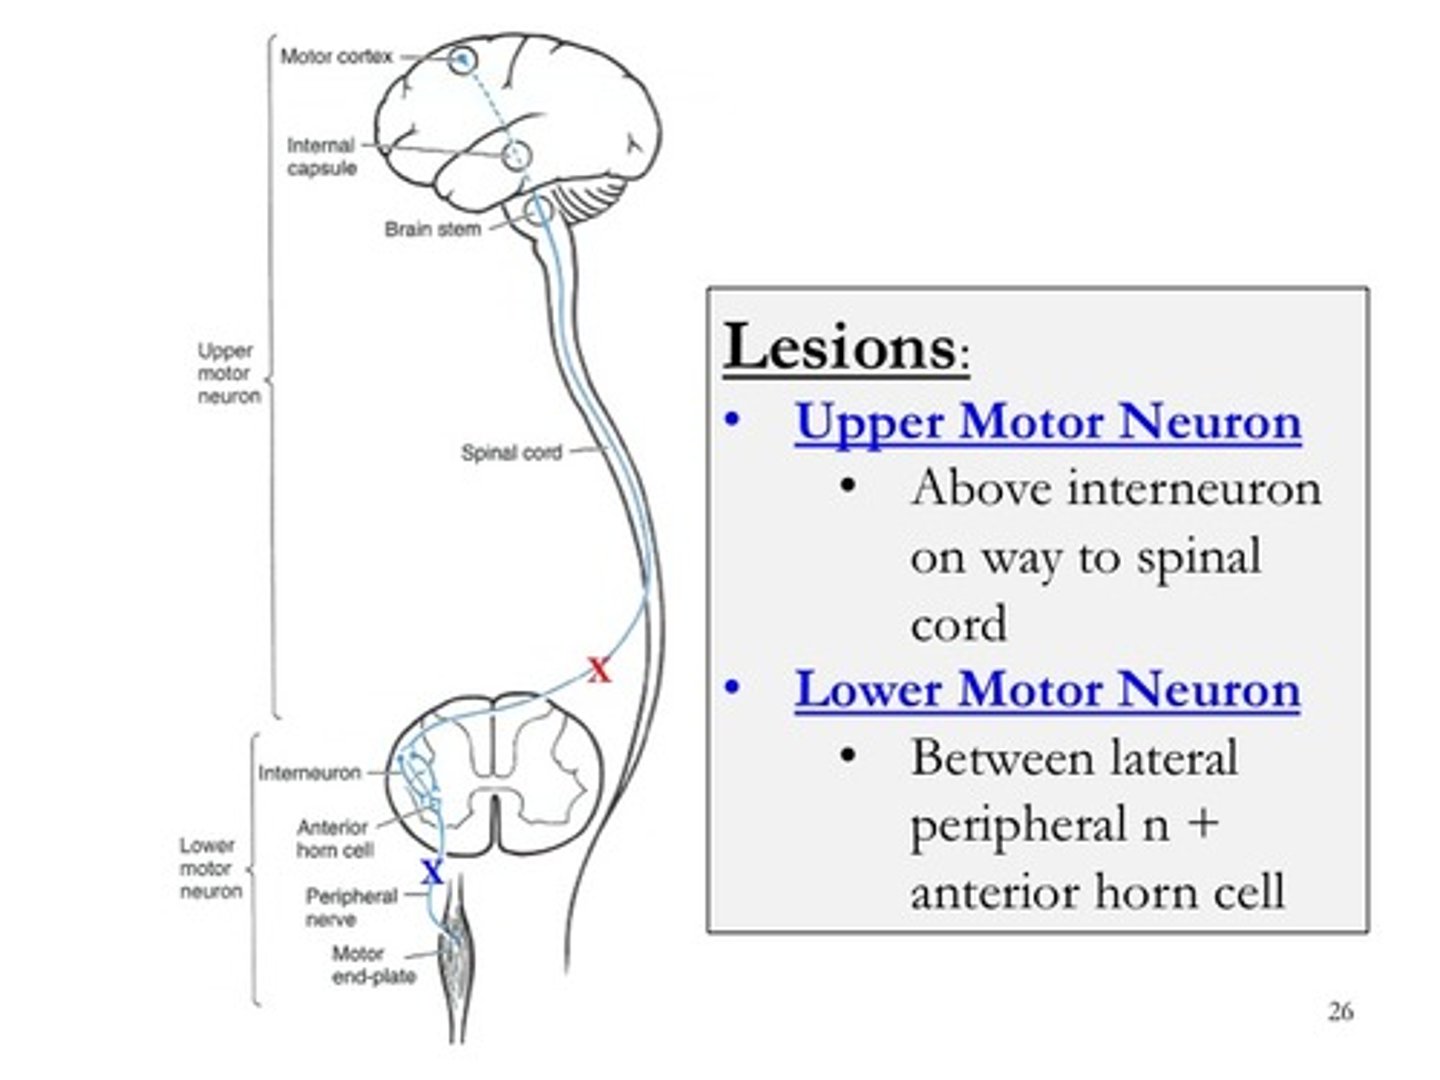

Hyporeflexia, hypotonia, atrophy, fasciculations

LMN Damage